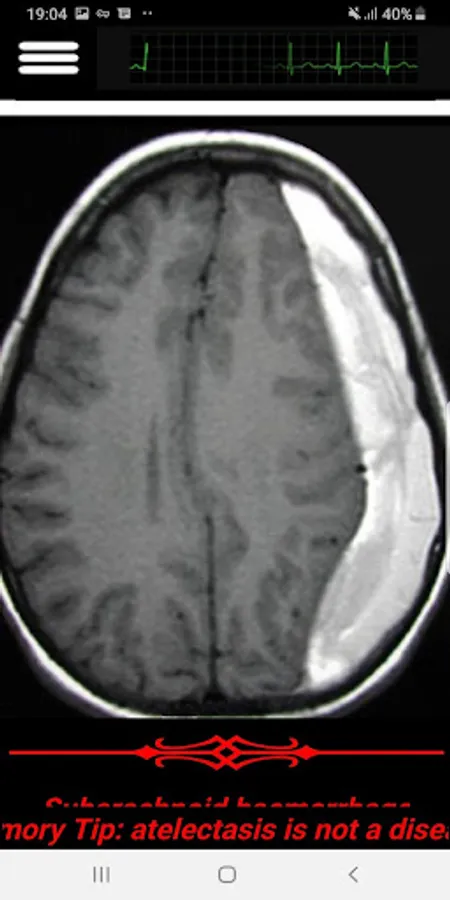

In this app, I covered the most important Head CT-Scan features that a practitioner face in his clinic or in an ER. Subjects like Hoe to read in an organize way, Blood, cisterns, Brain, Ventricles and bone.